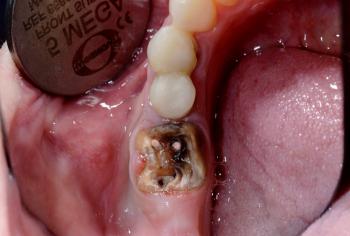

At Emergency Dentist Sydney, we provide 24-hour, 7-day emergency dental care to relieve pain quickly and prevent long-term damage. Whether you are experiencing intense toothache, a broken or knocked-out tooth, or dental trauma from an accident or sporting injury, our experienced team is available to help you immediately.

Severe Toothache & Infection Relief

Broken, Cracked & Knocked-Out Teeth

Emergency Extractions